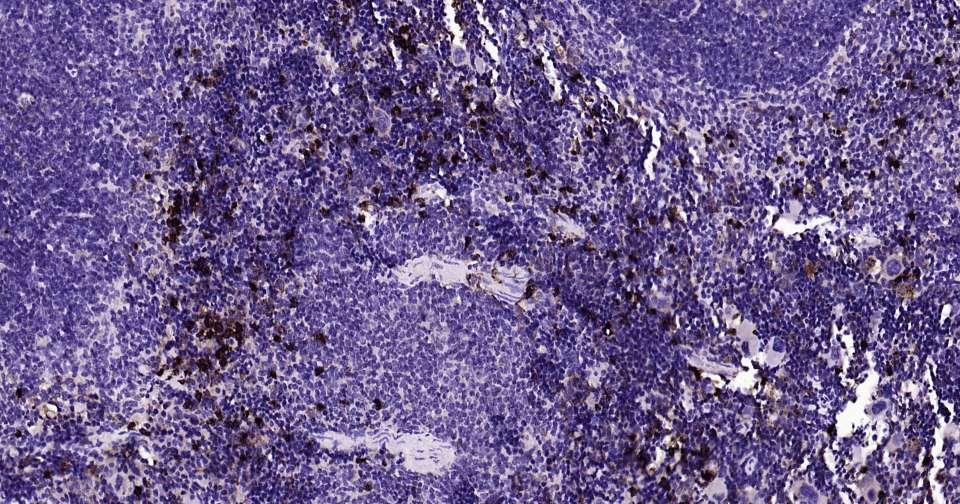

Immunohistochemical analysis of paraffin embedded mouse spleen tissue slide using IHC0335 (S100A8 Kit).

Immunohistochemical analysis of paraffin embedded human spleen tissue slide using IHC0335 (S100A8 Kit).

Immunohistochemical analysis of paraffin embedded human skin cancer tissue slide using IHC0335 (S100A8 Kit).

Immunohistochemical analysis of paraffin embedded human lung cancer tissue slide using IHC0335 (S100A8 Kit).